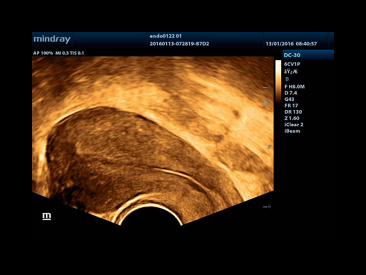

iBeamTM

Permits use of multiple scanned angles to form a single image, resulting in enhanced contrast resolution and improved visualization.